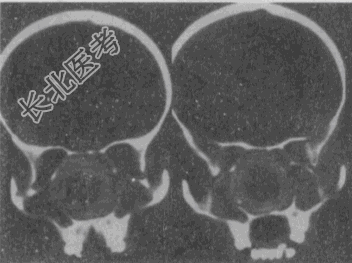

- 单项选择题女,14岁, 渐进性鼻塞2年余,右眼肿痛数月, CT如图所示,最可能的诊断是

A、筛骨骨肉瘤

B、筛骨骨纤维结构不良

C、筛骨软骨瘤

D、筛骨结核

E、筛骨骨化性纤维瘤